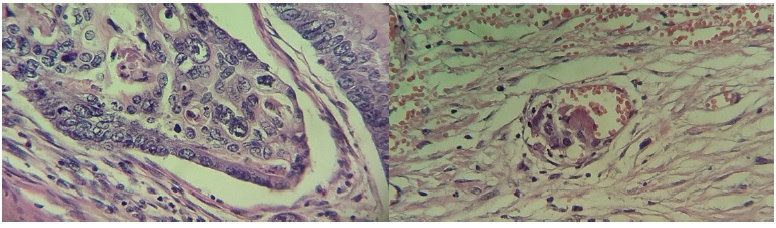

Se realizó una laparotomía exploradora en las siguientes 12 horas, donde se encontró un absceso de pared que disecaba la fascia aponeurótica del recto abdominal y los transversos del abdomen. El origen del absceso dependía de una tumoración en colon transverso (10 x 11 cm) con penetración hacia pared abdominal e invasión a la pared de yeyuno proximal (sin oclusión del mismo) y epiplón mayor. Se realizó una resección del tumor y colon transverso (Figura 4), así como epiplón mayor. Debido a que el tumor invadía la pared del yeyuno y a que una eventual resección en bloque haría necesaria una entero-entero anastomosis de alto riesgo (albumina 1,6 g/dL) se decide dejar márgenes con tumor macroscópico (R2) a dicho nivel. Finalmente se realizó una colostomía de segmento ascendente del colon. Se cierra la pared abdominal solo en la porción de la piel y se espera a que mejoren condiciones para una cirugía de revisión. Sin embargo, el paciente presenta deterioro progresivo, con falla y colapso cardiopulmonar refractario a las 48 horas del postquirúrgico.

El departamento de Anatomopatología reporto la pieza como un adenocarcinoma de tipo intestinal moderadamente diferenciado con extensión hasta los tejidos blandos pericolónicos e invasión vascular (Figura 5 y 6).